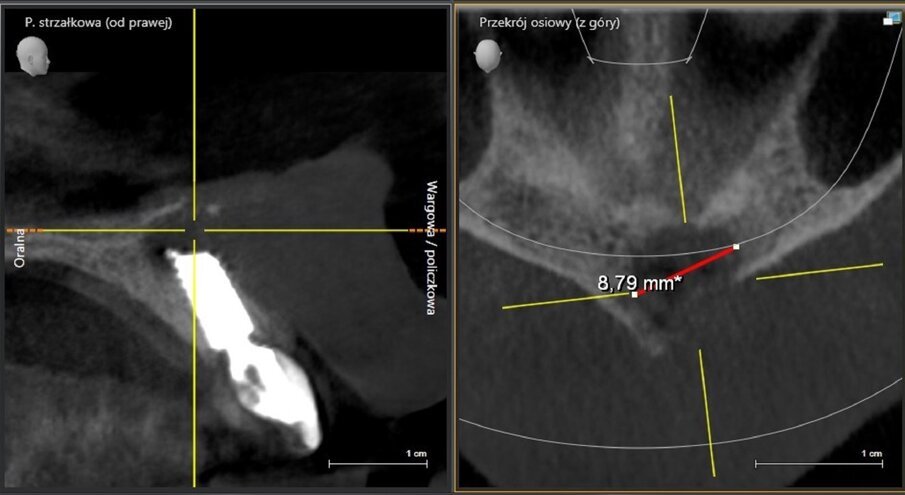

The implant apicectomy in Case 3 shows that one year after the immediate implantation with immediate loading there was inflammation around the implant apex. The rest was properly integrated (Figs. 13–20).

Fig. 14: Bone defect of 9.27mm in diameter.

Fig. 18: CBCT scan on the day of surgery. No bone augmentation.

Fig. 19: CBCT scan 1.5 years post-op. Visible bone regeneration.